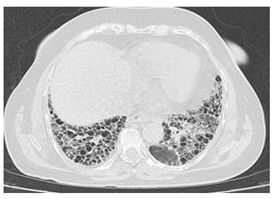

| Type of SARD-ILD | HRCT Features | Axial HRCT Images in Patients with SARD-ILD | Description of HRCT Images in Patients with SARD-ILD |

| SSc-ILD | NSIP, UIP with straight-edge sign and/or “four corners” sign. | ![]() | NSIP, which is the most common appearance in patients with SSc-ILD, is characterized by reticular opacities arranged in bands that run parallel to the lung’s subpleural contour, with a tendency to avoid the subpleural area. |